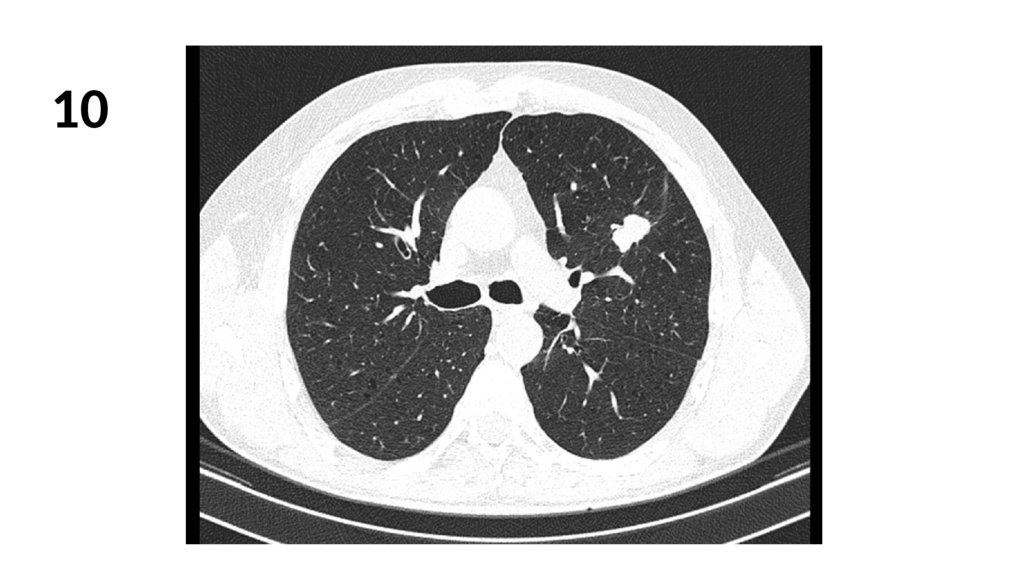

10.

10